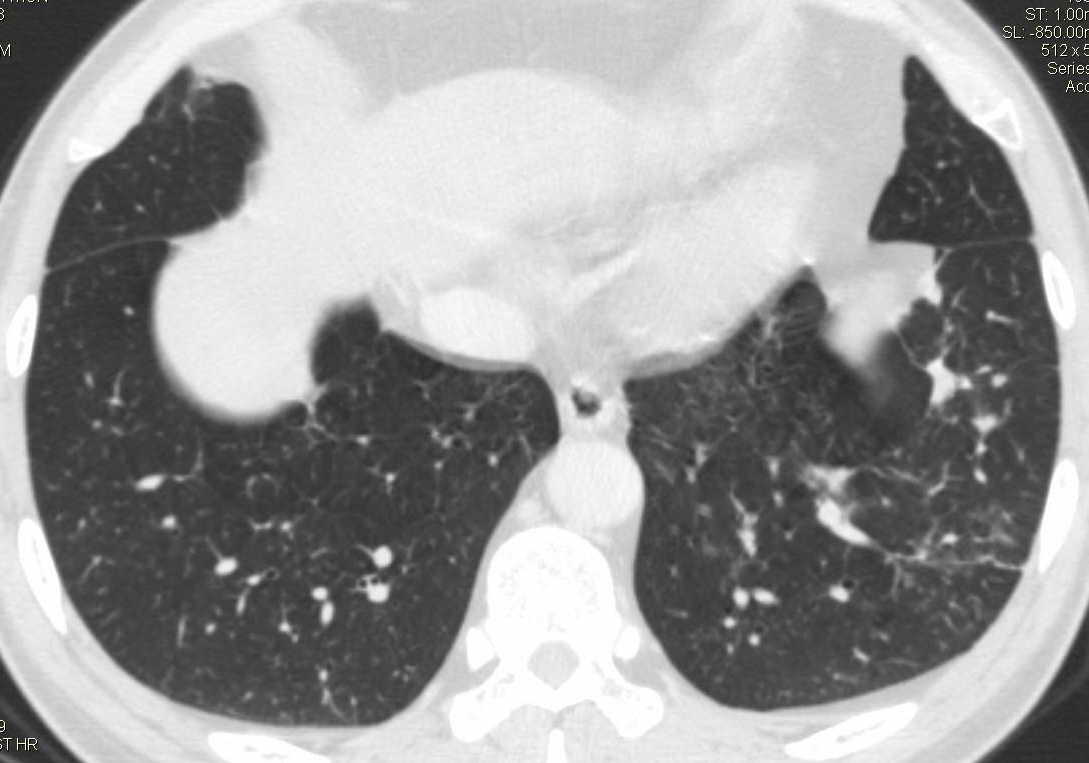

标题: CT15857:男性 58岁 咳痰带血 无发热 请各位大侠发表一下意见 [打印本页]

标题: CT15857:男性 58岁 咳痰带血 无发热 请各位大侠发表一下意见

两肺下叶肺纹理增多、增粗并呈“树芽状”改变。支气管扩张呈囊状,部分呈柱状改变。其周围可见散在的斑片样及条索样密度增高影,右肺下叶近叶间胸膜可见一形态不规则的高密度结节影,并与胸膜粘连。

考虑:支扩并发感染。

双肺多发炎性病灶,结核可能性大,建议抗炎治疗复查.右肺下叶前基底段结节灶,高度警惕肺癌可能

双肺间质性改变(间质纤维化?)伴支扩。右肺下叶有毛刺的小结节,考虑周围型肺癌可能性。